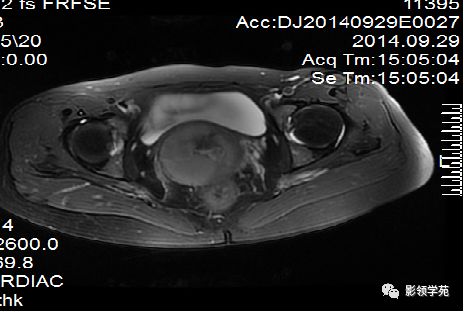

DWI:局限性高信号,癌组织ADC值<癌旁组织<小于正常宫颈组织

宫颈癌术后复发患者,DWI上病灶较T2 fs及T1+C更加明显